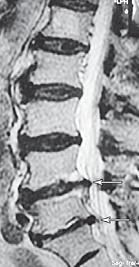

МРТ № 2

На МРТ № 2 — грудной отдел в состоянии «норма»

Грудной отдел должен иметь нормальную степень кифоза (угол кифоза по Stagnara формируется линией, параллельной замыкательным пластинкам ТIII и ТXI= 25°). Позвоночный канал на грудном уровне имеет округлую форму, что делает эпидуральное пространство узким почти по всей окружности дурального мешка (0,2–0,4 см), а на участке между TVI и ТIX он наиболее узок. Сагиттальный размер: ТIХI = 13–14 мм, ТXII = 15 мм. Поперечный диаметр: > 20–21 мм.

Высота межпозвонковых дисков: самая меньшая на уровне ТI, на уровне ТVIХI приблизительно 4–5 мм, наибольшая на уровне ТХIХII.